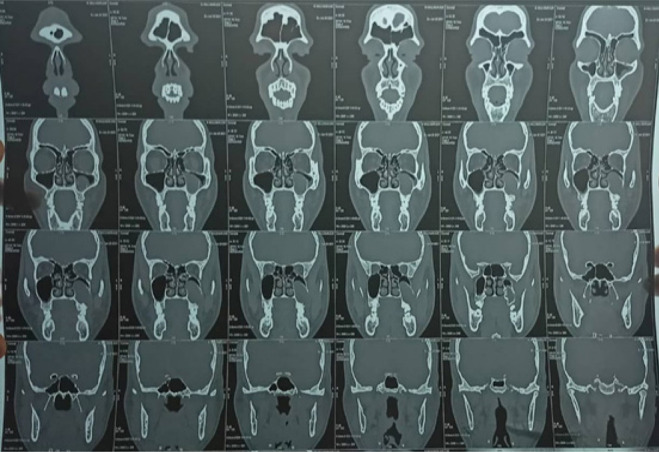

Odontogenic keratocyst is a benign intraosseous lesion of odontogenic origin which is characterized by its aggressive nature. It is usually present in the mandibular posterior area, although it can also be found in the maxilla, particularly in the canine region. We discuss a unique example of OKC in the maxillary sinus involving the 27&28 region. Due to comparable clinical signs, this lesion is more prone to be mistaken for other lesions of the maxillary sinus, such as sinusitis or polyps. On the other side, this benign disease has the potential to develop into Ameloblastoma or squamous cell carcinoma. A favorable prognosis thus depends on early identification, precise diagnosis, appropriate treatment, and follow-ups.